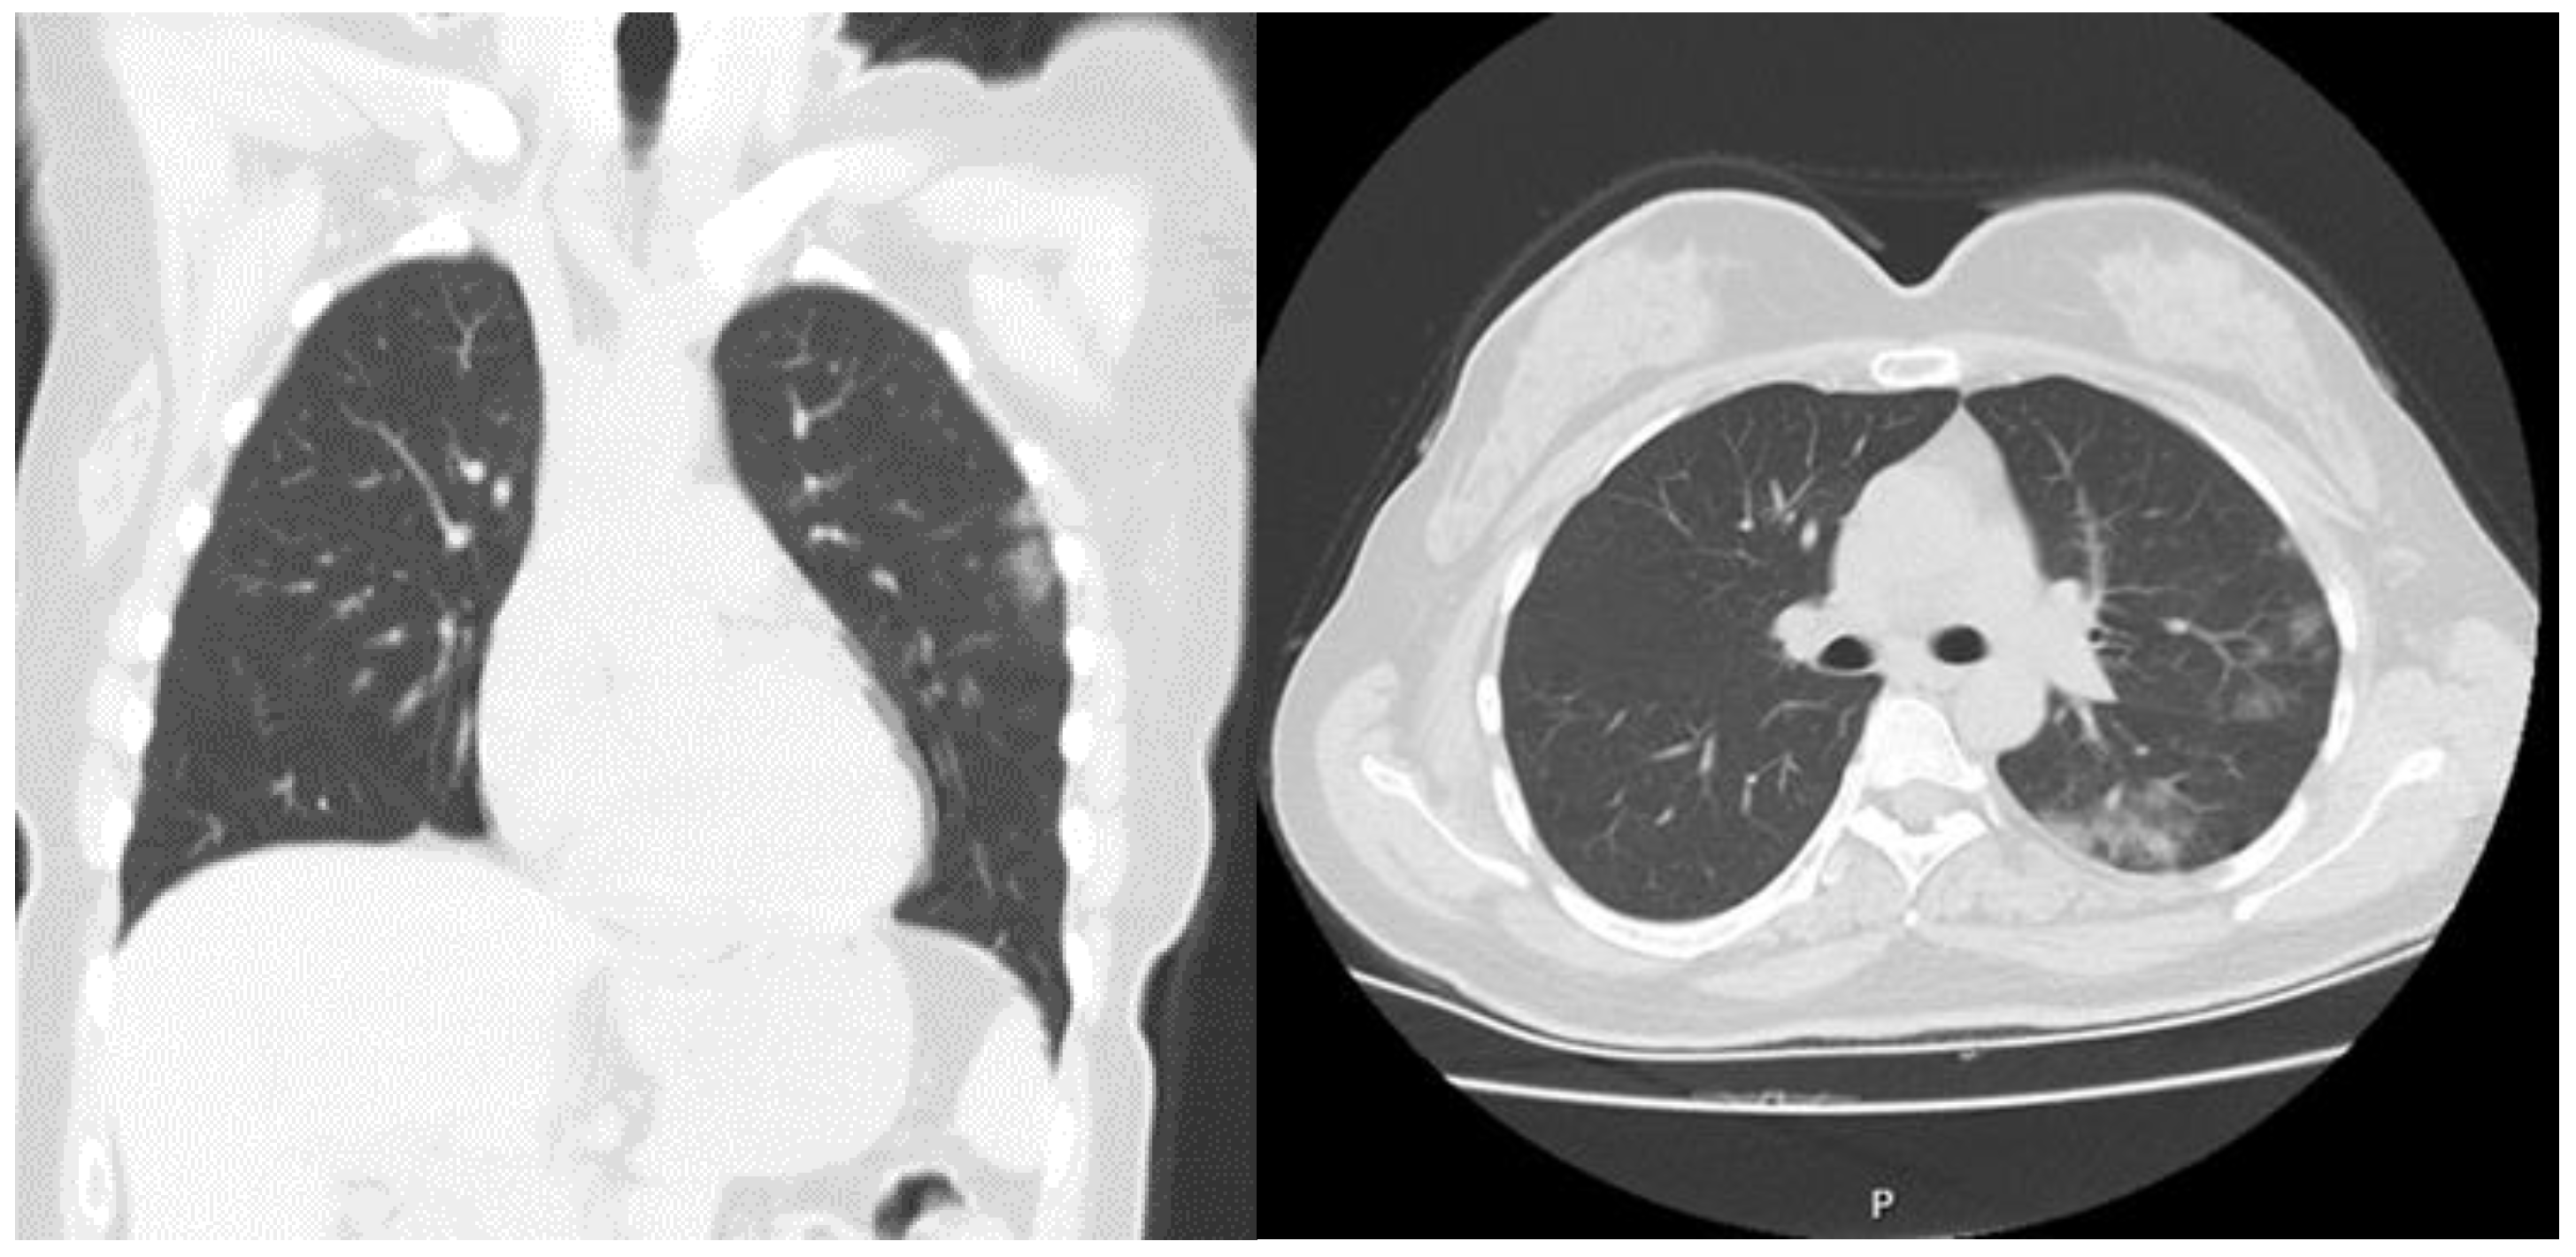

| Chest Computed Tomography | ||

| Normal | 74 (21.3) | 0 |

| Mild | 95 (27.4) | 0 |

| Moderate | 138 (39.8) | 15 (20.8) |

| Severe | 40 (11.5) | 57 (79.2) |